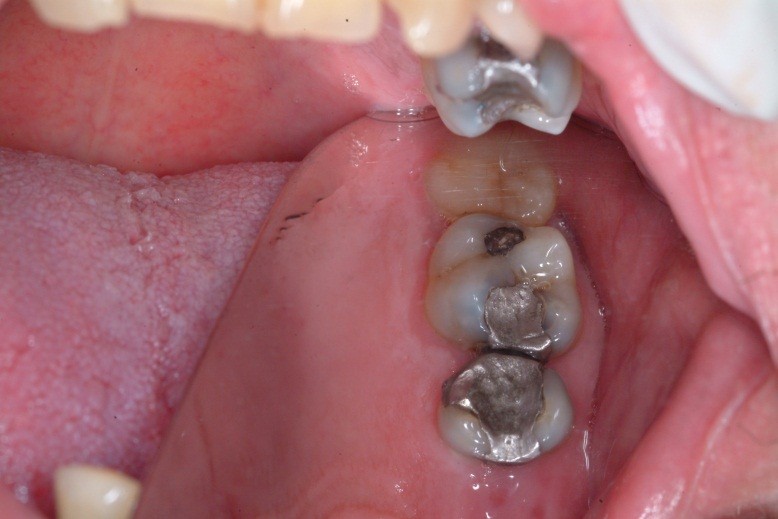

A toothache caused by a broken tooth (tooth fracture) without associated cavity or advanced gum disease. Biting on the area of tooth fracture can cause severe sharp pains. These fractures are usually due to chewing or biting hard objects such as hard candies, pencils, nuts, etc. Sometimes, the fracture can be seen by painting a special dye on the cracked tooth. Treatment usually is to protect the tooth with a crown. However, if placing a crown does not relieve pain symptoms, a root canal procedure may be necessary.